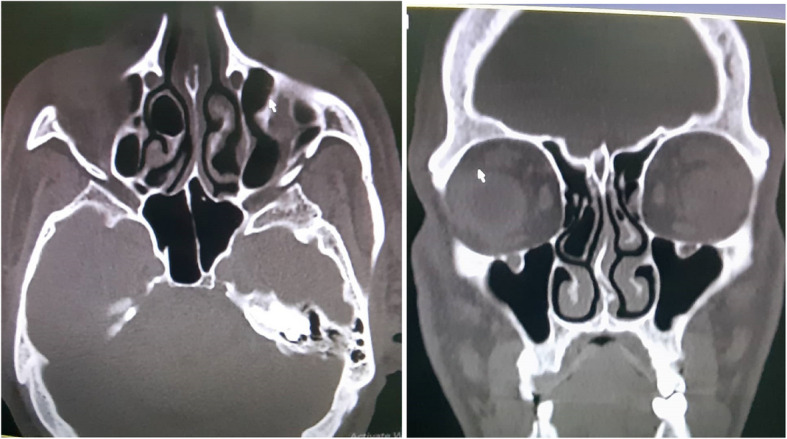

Objective: Concha bullosa, a common anatomical variation characterized by air-filled cavities in the turbinate bones, can influence sinonasal function and surgical planning. This study aims to evaluate the distribution, laterality, and cranial skeletal type associations of concha bullosa (CB) among patients with confirmed CB findings on computed tomography (CT) scans.

Methods: A retrospective cohort study was conducted on 774 patients who underwent cranial and facial CT scans between March 2023 and March 2024. Patients were classified into mesocephalic, brachycephalic, and dolichocephalic groups based on the cephalic index. The distribution and laterality of concha bullosa were assessed using CT scans, and statistical analyses were performed using the Chi-square test, with a significance level set at P < 0.05.

Results: Among CB-positive patients, left-sided concha bullosa was most common (49.48%), followed by right-sided (31.91%) and bilateral (18.6%) involvement. Mesocephalic individuals constituted the largest proportion of CB-positive cases (55.56%), followed by dolichocephalic (22.86%) and brachycephalic (21.57%) individuals. A significant gender difference was observed in the mesocephalic (P = 0.001) and brachycephalic (P = 0.013) groups, with males exhibiting a higher prevalence of right-sided and bilateral concha bullosa.

Conclusion: Concha bullosa distribution varies significantly among cranial skeletal types among CB-positive patients, with mesocephalic individuals exhibiting the highest overall prevalence. Our findings underscore the influence of cranial morphology on the presentation of CB. This insight may enhance radiological evaluation and individualized surgical planning in CB-positive patients.